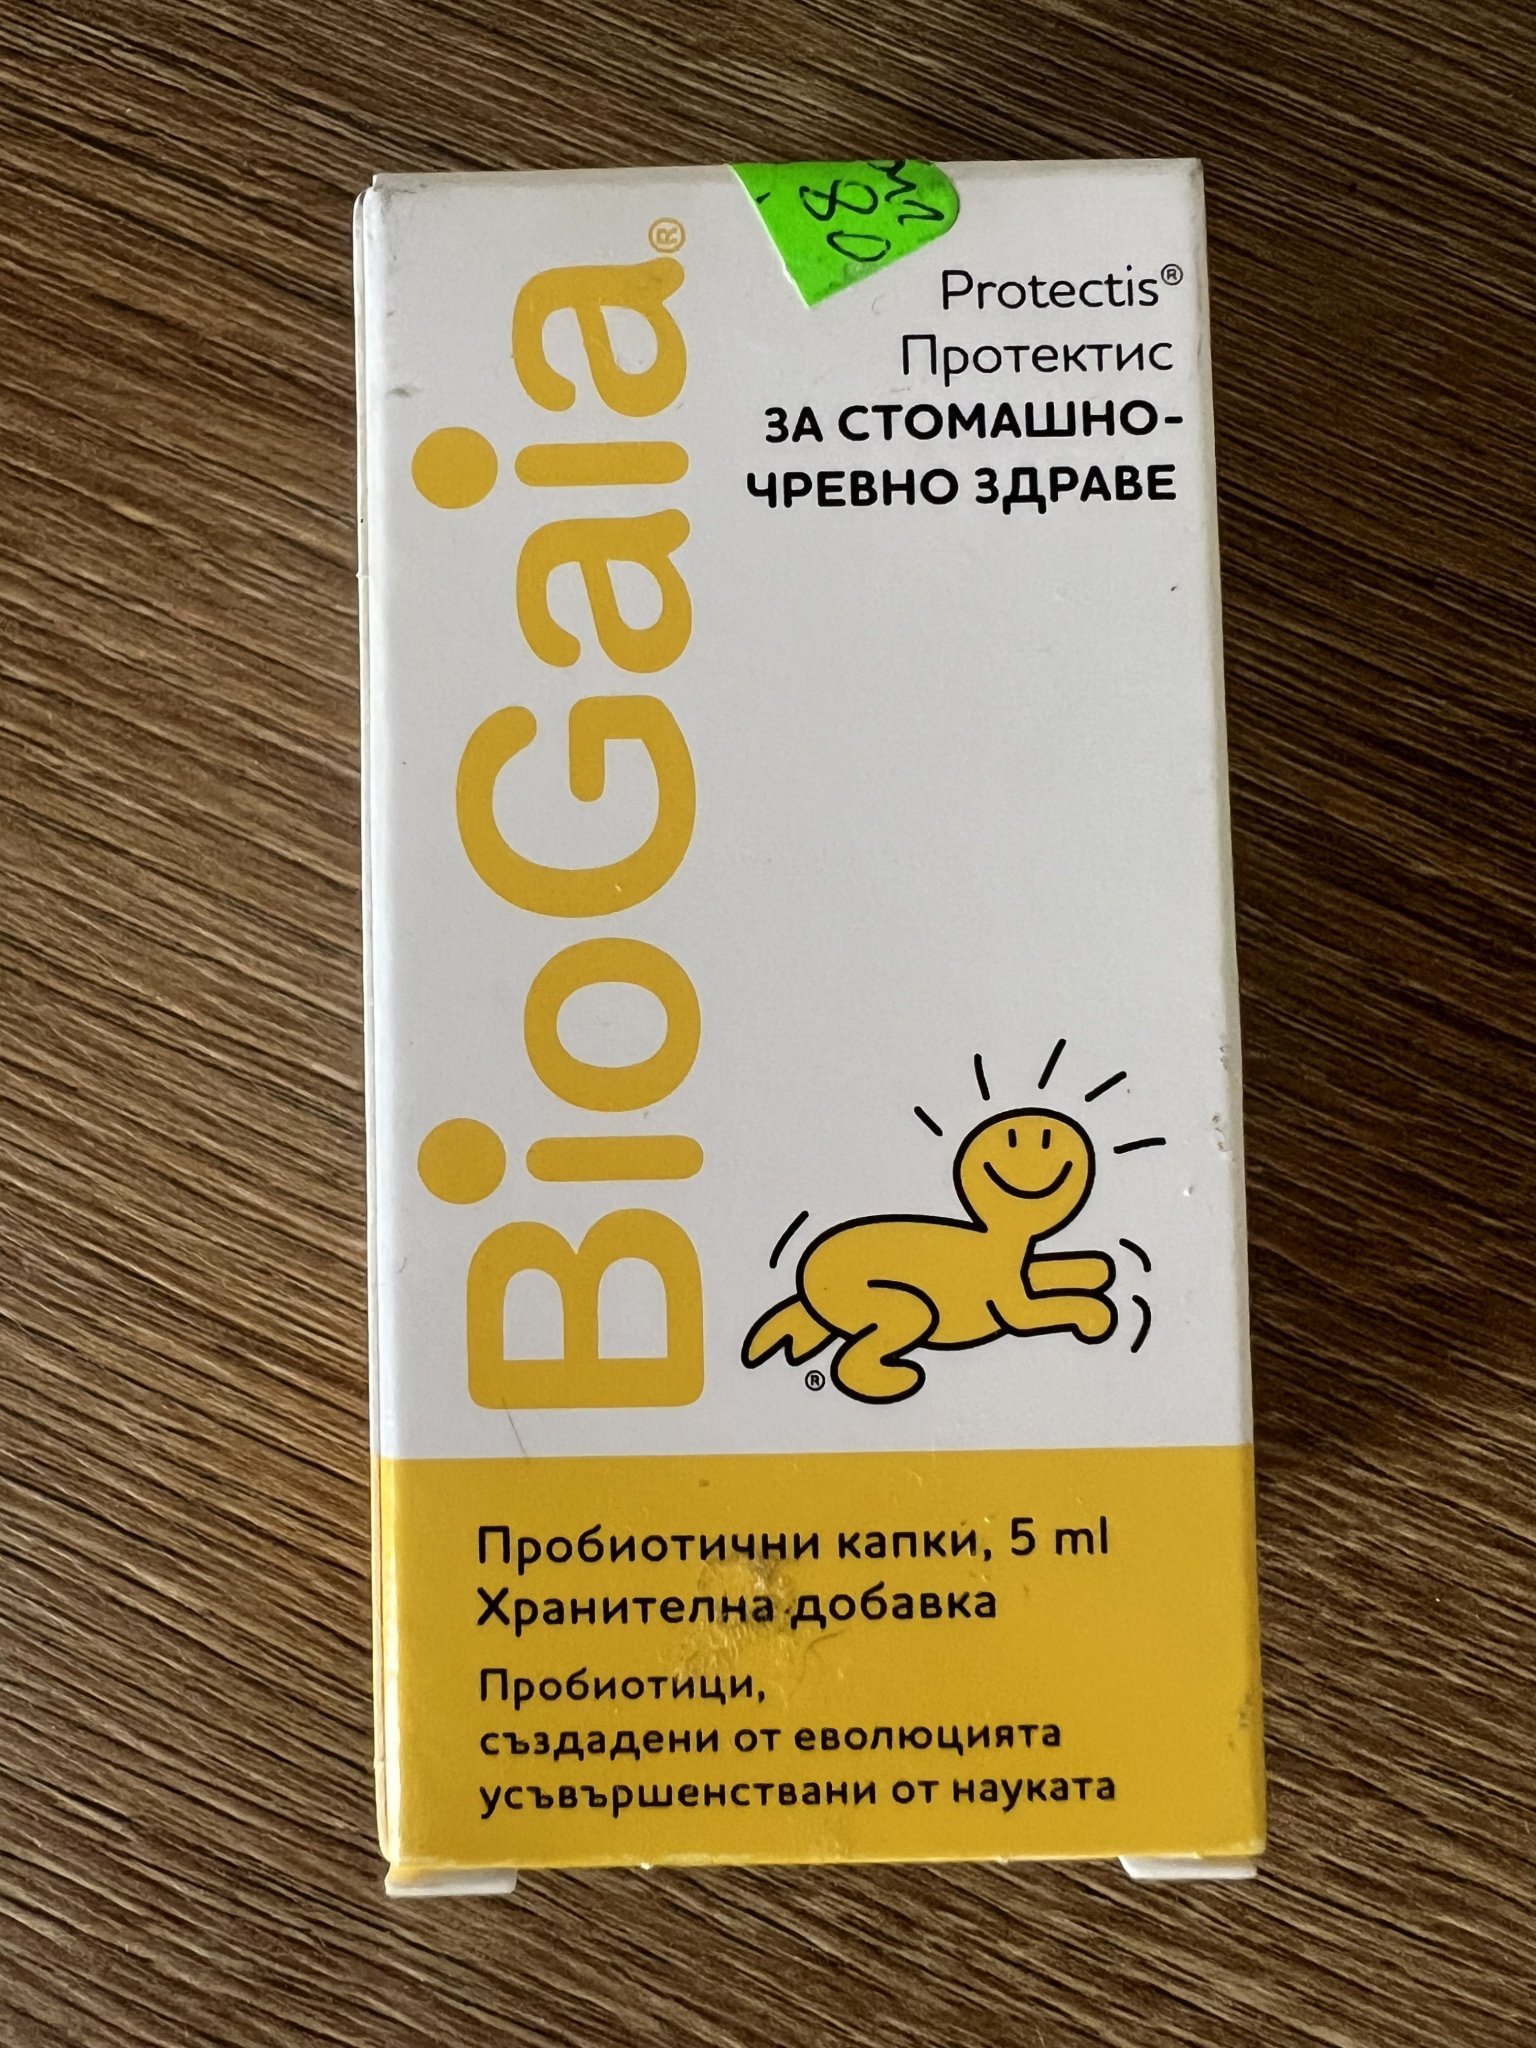

Четох инструкциите ,никъде не пише . А са капки за 30 лв 😁

Четох инструкциите ,никъде не пише . А са капки за 30 лв 😁